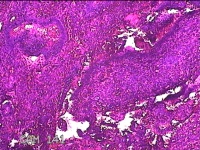

性别

女

年龄

35岁

临床诊断

异常子宫出血:①子宫内膜息肉 ②子宫内膜憩室 ④子宫内膜炎

一般病史

阴道不规则流血9个月。

标本名称

宫腔内组织

大体所见

灰白暗红色不规则碎组织2.3x2x0.8cm一堆。